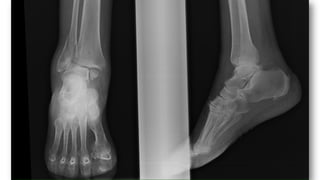

FRACTURASDE TOBILLO

• Fracturas en supinación-rotación externa (60%)

• Fracturas en supinación-aducción (20%)

• Fracturas en pronación-rotación externa y pronación-

abducción (20%)

• Fracturas en pronación-dorsiflexión.

• A. Fractura unimaleolar (de tibiao

peroné)

• B. Fractura bimaleolar

• C. Fractura equivalentebimaleolar

• D. Fractura trimaleolar

• TratamientoQuirúrgico: En lesiones

de dos complejos, fracturas

inestables o desplazadas. Resto: tto

conservador